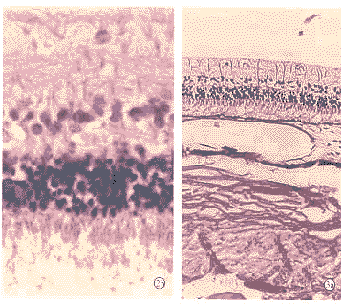

2.1正常对照组(图1) 对照组视网膜组织排列整齐,各层次结构清晰。光感受器细胞与色素上皮细胞(retinal pigment epithelium,RPE)紧密相连,形态正常,无变性。神经节细胞数量和排列正常,无空泡样变性,神经纤维层清晰。M%26uuml;ller细胞框架纤维结构完整。

2.2 RD对照组(图2) 光镜下2眼视网膜神经上皮层与RPE层分离。部分RPE细胞游离。光感受器细胞结构显著紊乱,断裂,参差不齐,大量空泡样变性。内外核层水肿,空泡样变,有核周空泡和核固缩。内外网状层结构紊乱。神经节细胞和神经纤维水肿,部分细胞有核固缩。大部分M%26uuml;ller细胞的纤维支架结构消失。

图1 正常对照组(×40) 图2 RD阳性对照组(a ×10);b:光感受器结构紊乱,神经节细胞水肿和空泡样变,M%26uuml;ller细胞支架纤维结构消失(×40) 图3 1周实验组(a ×10);b:光感受器排列紊乱,内核层和神经细胞层水肿,空泡出现(×40) 图4 2周实验组内核层和神经节细胞均有空泡样变(×40) 图5 3周实验组见部分内核层和神经细胞有核固缩,核周空泡现象(×40) 图6 4周实验组见视网膜结构光镜下结构清晰正常,与对照组相比无明显差异(×40) Fig.1 Normal control group(×40) Fig.2 RD control group (a ×10); b:disturbance of photoreceptor cells,swelling and vacuole of ganglion cells,disappearance of fiber structure of M%26uuml;ller cells Fig.3 1 week experiment group (a ×10); b:disturbance of photoreceptor cells,swelling and cava appearance of inner nuclear layer and ganglion cells Fig.4 2-week experiment group:vacuolar degeneration in inner nuclear layer and ganglion cells(×40) Fig.5 3-week experiment group:nucleus and cytoplasm shrink in part of inner nuclear layer and ganglion cells (×40) Fig.6 4-week experiment group:normal appearance and clear structure of retina,compared to normal control with no obvious difference (×40)